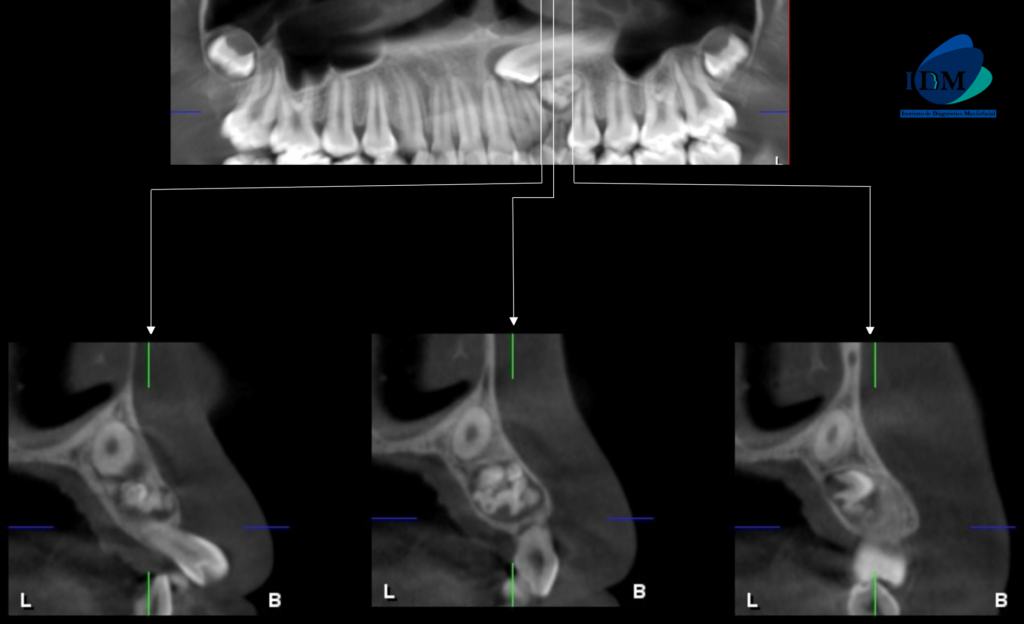

A la evaluación de la tomografía volumétrica (CBCT) en los cortes axiales (Figura 2) y transaxiales (Figura 3), se aprecia imágenes hiperdensas (dentículos) circunscrita con un halo hipodenso, localizada entre los segmentos radiculares de piezas 22 y 24, de limites definidos ocasionando desplazamiento de pieza 23, adelgazamiento de tabla ósea vestibular y palatina compatible con odontoma compuesto. Imagen hiperdensa circunscrita con un halo hipodenso, localizada entre los segmentos radiculares de piezas 73 y 35, de limites definidos, forma irregular, ocasionando el desplazamiento de piezas 34 y 33, adelgazamiento de la tabla ósea vestibular y lingual compatible con odontoma complejo.

CORTES TRANSAXIALES